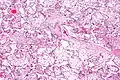

| Micrograph of villous immaturity. H&E stain. | |

Immature chorionic villi are larger and have more central blood vessels; thus, the diffusion distance for gas and nutrient exchange is larger and, therefore, placental function is impaired.

Low mag.